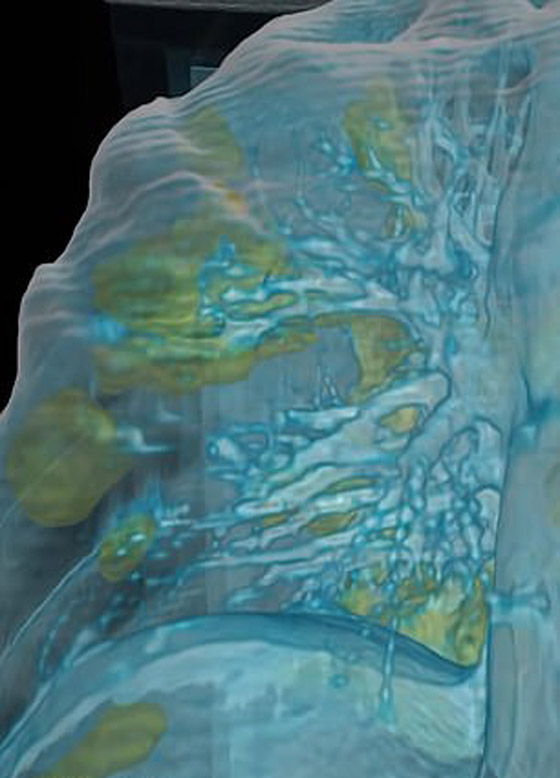

تصوير مقطعي محوسب من مستشفى جامعة جورج واشنطن يُظهر آثار فيروس كورونا المستجد، أو ما يُعرف بـ"كوفيد-19" رئتي رجل عمره 59 عاماً. فشاهدوا معنا في الفيديو المدهش أدناه كيف تبدو رئة مصاب بفيروس كورونا (فيروس كوفيد 19) وما يحصل داخلها..